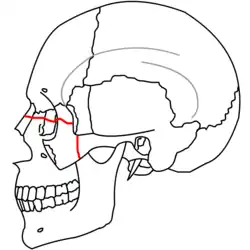

| Fraturas 2 de Le Fort | |

No início do século XX, René Le Fort mapeou as regiões faciais típicas dos traumas maxilo faciais, agora conhecidos como Fraturas I, II, e III de Le Fort (direita).[11] A Fratura I de Le Fort, também chamada de Fratura de Guérin ou Fratura transversa,[12] envolve a maxila, separando-a do palatino.[13] A Fratura II de Le Fort, conhecida também como Fratura piramidal,[12] atravessa os ossos nasais e o aro orbital.[13] A Fratura III de Le Fort, por sua vez, chamada também de Disjunção crâniofacial,[12] atravessa a frente da maxila e envolve as suturas zigomaticofrontal, maxilofrontal nasofrontal, os assoalhos das órbitas, a etmóide e o esfenóide.[12] As Fraturas de Le Fort, responsáveis por 10-20% das fraturas faciais, são frequentemente associadas com outros ferimentos graves.[13] Le Fort fez seu trabalho com base em cadáveres e caveiras, e o sistema de classificação tem sido criticado como impreciso e simplista uma vez que a maioria das fraturas de meia-face envolvem uma combinação das fraturas de Le Fort.[13] Embora a maioria das fraturas faciais não seguem os padrões descritos por Le Fort, seu sistema ainda é utilizado para categorizar os diversos tipos de traumatismos.[14] http://www.angelfire.com/nm/cirurgia/pritra/Image90.gif